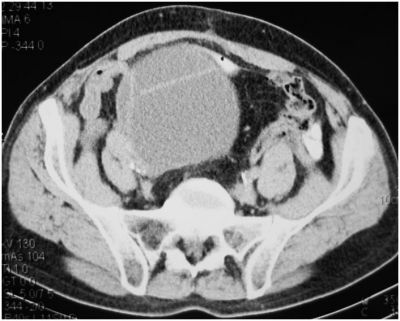

КТ через 6 месяцев (наполненный мочевой резервуар)